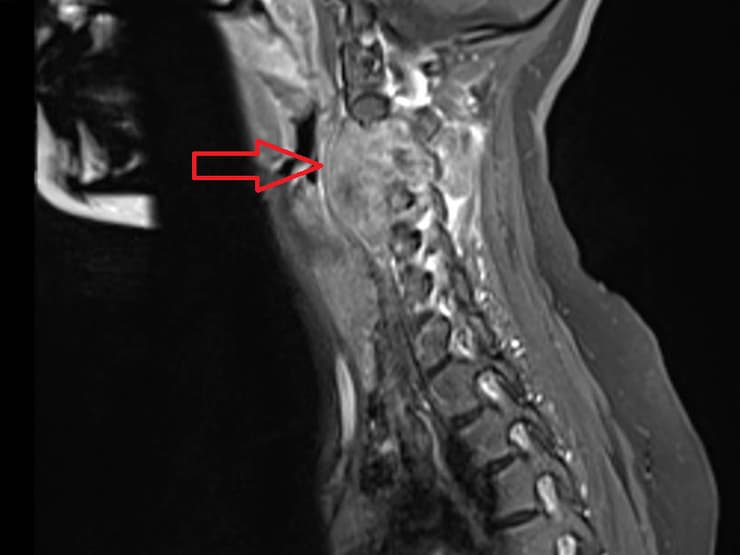

למזלה, היא הייתה התמימה היחידה במה שיתפתח לסיפור חיים דרמטי. האורתופד חשד והפנה את שני ל-MRI. התוצאות היו קשות וגילו ששני חולה בסרקומה ע"ש יואינג (Ewing sarcoma), סרטן עצמות ששכיח בילדים, בני נוער וצעירים. "הרגשתי שאני בסיוט והכול סביבי החשיך", משחזרת האם,, "שלושה ימים התנהלתי על אוטומט ואז קראתי את עצמי לסדר. סופי, די. צאי מזה. מעכשיו את תנהלי את האירוע הזה - לא הוא אותך". וכך היה לאורכן של שמונה השנים שבהן בתה הייתה חולה.

יואינג סרקומה מופיעה בילדים ובצעירים בטווח הגילים 20-10, ועיקר תסמיניה הם כאב במקום הגידול. מחלתה של שני התפתחה בחוליה צווארית C3, שקרובה לגולגולת. "בשל מיקומו הבעייתי והמאתגר של הגידול, נדרשת מיומנות טכנית גבוהה, ניסיון והרבה סבלנות".